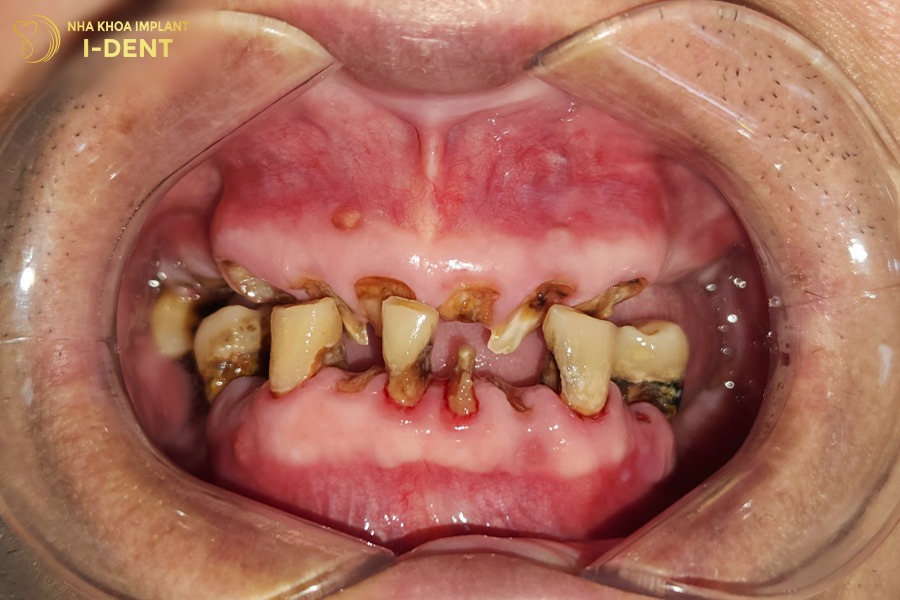

Vì chủ quan trong việc chăm sóc răng miệng, thêm thói quen hút thuốc khiến chú Nguyễn Hải mắc bệnh lý viêm nha chu nặng. Lâu ngày gây tiêu xương và làm lung lay, gãy rụng răng gần hết cả 2 hàm.

Tình trạng răng ban đầu của chú Nguyễn Hải

Với tình trạng này, bác sĩ Tín đã tiến hành điều trị nha chu và nhổ các răng lung lay để ngăn ổ nhiễm trùng lan rộng trước. Sau đó chỉ định phương án cấy ghép Implant All-on-4 cho cả hai hàm, đặt 4 trụ Implant cho 1 hàm và phục hình 12 răng sứ lên trên, nhằm đảm bảo thẩm mỹ cũng như chức năng ăn nhai chắc chắn cho chú.